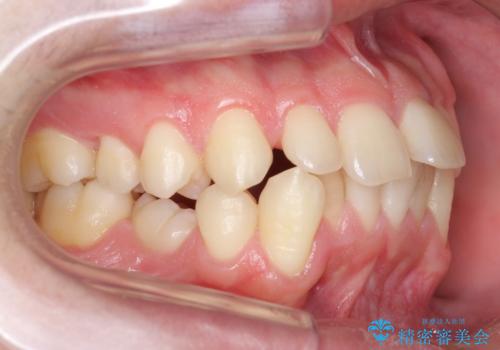

インプラントの前に矯正治療を行い、入れる隙間を確保しました。

矯正治療については以下を参照してください。

https://seimitsushinbi.jp/case/64227/